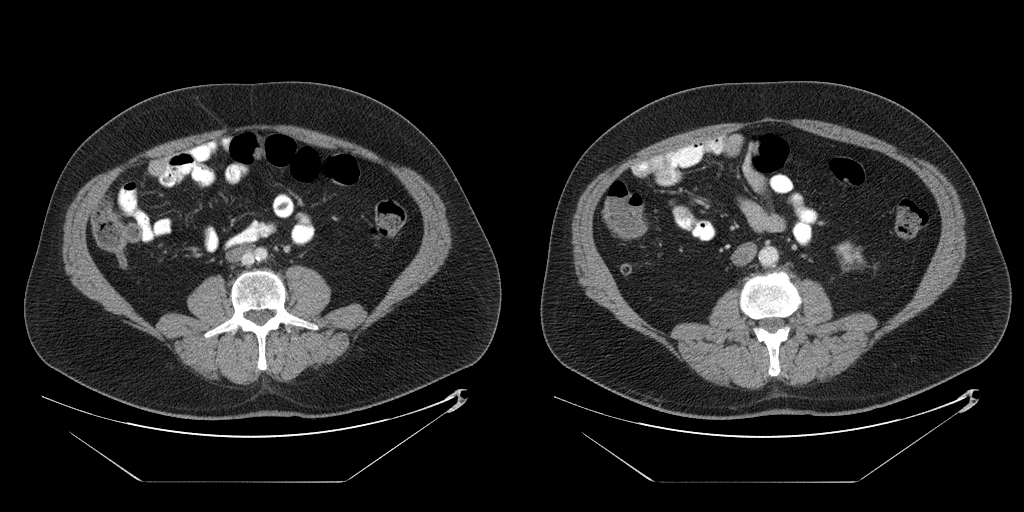

The full validation was then performed on Dataset B treating the two models as a single process that takes in a full abdominal CT series and produces estimates of body composition in terms of square cross-sectional area of muscle, subcutaneous fat, and visceral fat. In this case, the DSC is not an appropriate measure because the segmentation may be performed on a different slice from the ground truth mask. Table 2 compares the accuracy of the different tissue types and Figure 3 shows some example outputs.